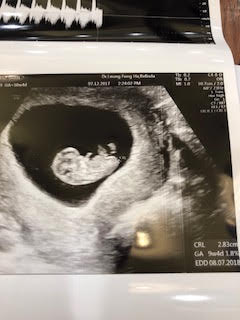

好不容易捱到 第8週,終於聽到 BB的心跳,以為身心可以鬆一口氣,原來鬼門關才剛打開門。接下來的日子,我持續地滲血,腹痛,瘋狂地孕吐,每天來回勉強進食與瘋狂嘔吐之間,加上滲血情況沒有改善,整個人陷於極度疲憊的狀態。